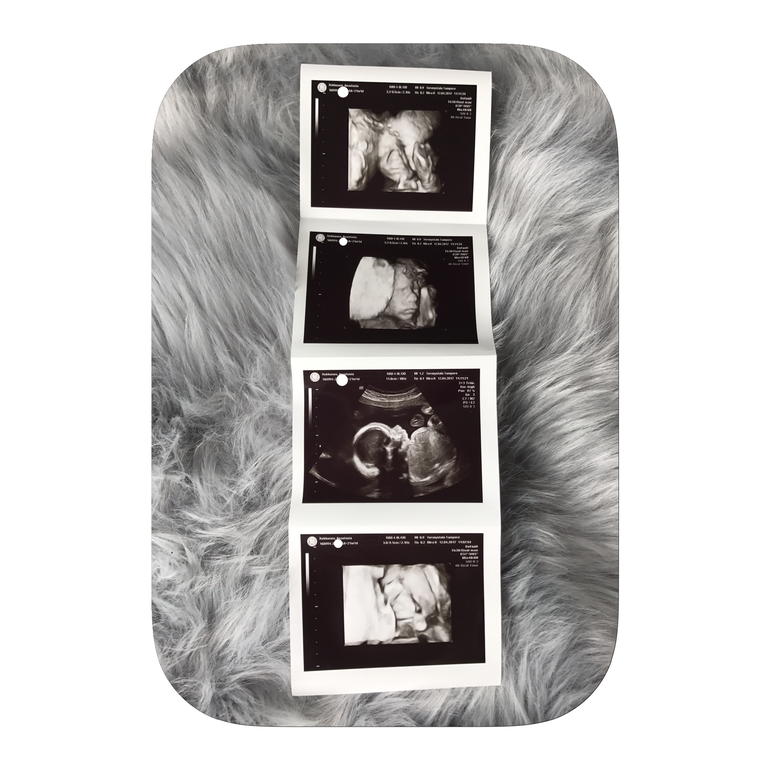

Все с ребеночком хорошо, здоровенький и активный! Она долго все смотрела, потому что ребеночек был в комочек завернут, закрывал руками и ногами лицо😅 но слава богу все удалось замерить. Весит мое счастье 439 грамм, прикрепление по задней стенке, плацента не перекрывает выход, слава богу! Сердцебиение 150. Соответствует сроку 21+2 а у меня 21+1, на денек опережает. В общем все хорошо!!!

Дата родов 22.8.2017.

Ну и фото: